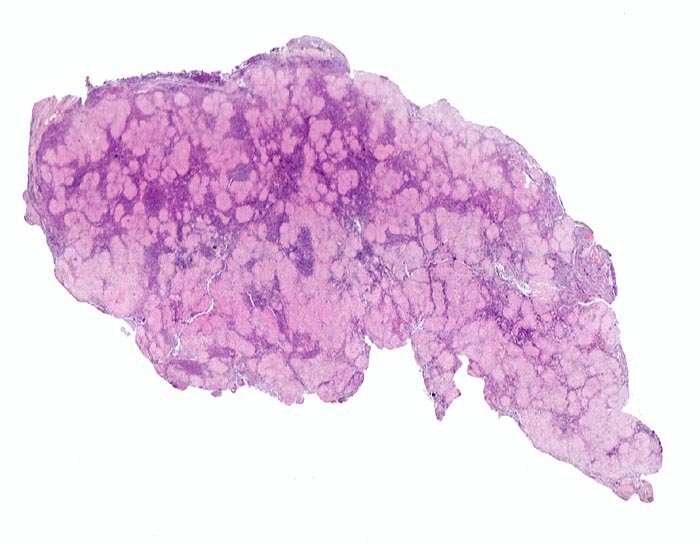

PathoPic ID 4012 - Lymphknotensarkoidose (Morbus Boeck)

Lymphknotensarkoidose (Morbus Boeck)

Systemerkrankung/Immunpathologie

Lymphknoten, inguinal

Lymphatische Gewebe, KM, Milz

Zahlreiche helle konfluierende Granulome durchsetzen das Lymphknotenparenchym.

Vergrösserte inguinale Lymphknoten bei bekannter Sarkoidose mit Befall der Lungen.

Histologie

Scan